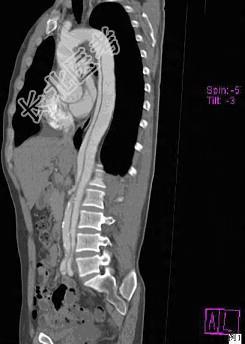

- 多项选择题请看一组主动脉的CT增强图像,正确的描述和结论是 ( )

A、主动脉血栓

B、主动脉瘤

C、主动脉夹层

D、真腔较假腔小

E、真假腔之间线状低密度影为内膜片影